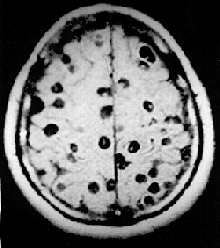

Neurocysticercosis /ˈnjʊəroʊˌsɪstiˌsɜːrˈkoʊsɪs/ is a specific form of the infectious parasitic disease cysticercosis that is caused by the infection with Taenia solium, a tapeworm found in pigs. Neurocysticercosis occurs when cysts formed by the infection take hold within the brain, causing neurologic syndromes such as epileptic seizures. It is a common cause of seizures worldwide. It has been called a "hidden epidemic"[1] and "arguably the most common parasitic disease of the human nervous system".[2] Common symptoms of neurocysticercosis include seizures, headaches, blindness, meningitis and dementia.[3]

Neurocysticercosis most commonly involves the cerebral cortex followed by the cerebellum. The pituitary gland is very rarely involved in neurocysticercosis. The cysts may rarely coalesce and form a tree-like pattern which is known as racemose neurocysticercosis, which when involving the pituitary gland may result in multiple pituitary hormone deficiency.[4]

Neurocysticerosis is diagnosed by computed tomography (CT) scan.[3] Diagnosis may be confirmed by detection of antibodies against cysticerci in CSF or serum[5] through ELISA or imunoblotting techniques.[6]